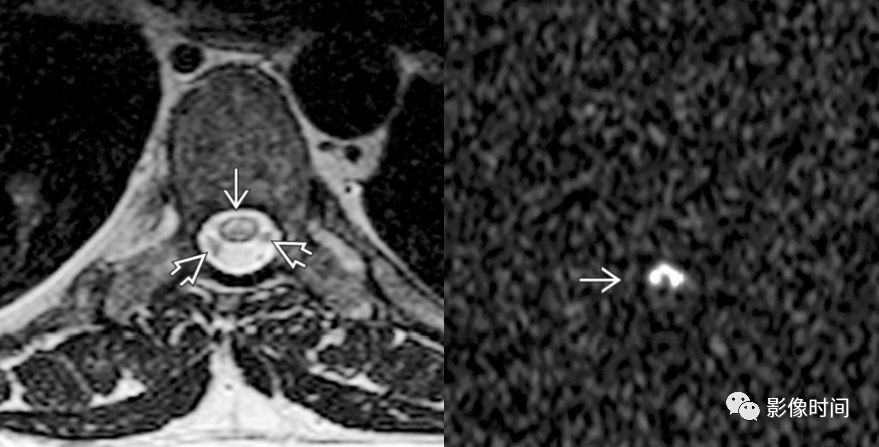

神经脊髓炎谱系疾病(neuromyelitis optica spectrum disorder,NMOSD):是一种由水通道蛋白-4(AQP-4)自身抗体介导的炎性脱髓鞘疾病,青年或中年女性较多见,临床常为双侧视神经炎和脊髓炎导致失明和截瘫,也可累及大脑。

MRI:

脊髓:病灶 T2WI 呈高信号,T1WI 呈稍低信号,急性期出现斑片状或云雾状强化,轴位常位于脊髓中央,长度>3 个椎体长度。亮点征:轴位 T2WI 很高信号的多发斑点,信号高于脑脊液,特异性=97%。

病灶分布于脊髓中央,长度大于3个椎体,亮点征